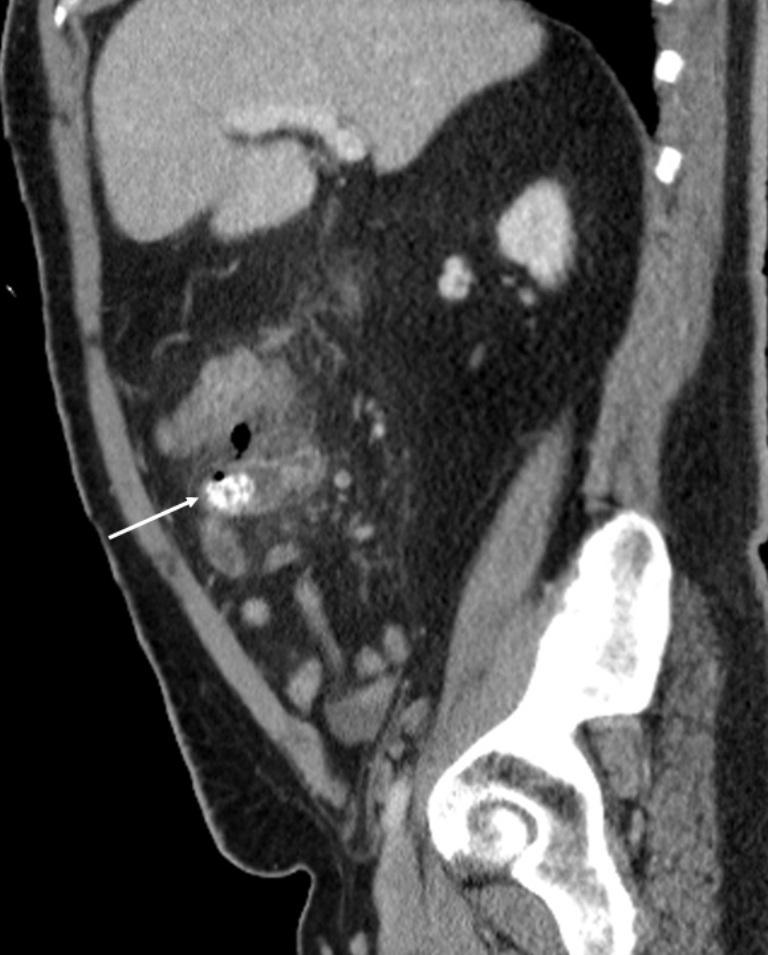

El divertículo de Meckel es la anomalía congénita más frecuente del tracto gastrointestinal, es un divertículo verdadero, ya que contiene todas las capas de la pared intestinal. Suele ser asintomático o se detecta de manera incidental en las pruebas de imágenes diagnósticas. Tiene un riesgo de complicación del 2-40%, siendo la más frecuentes la hemorragia, la obstrucción intestinal y la diverticulitis.

Se describe el caso de un paciente masculino de 52 años de edad, que consultó al servicio de urgencias del Hospital Universitario de Salamanca (España) por un cuadro de dolor abdominal, clínica infecciosa y  de obstrucción intestinal.

Mediante pruebas de imagen se diagnosticó una obstrucción intestinal secundaria a diverticulitis de Meckel por un enterolito, se realizó intervención quirúrgica y se confirmaron los hallazgos radiológicos descritos.